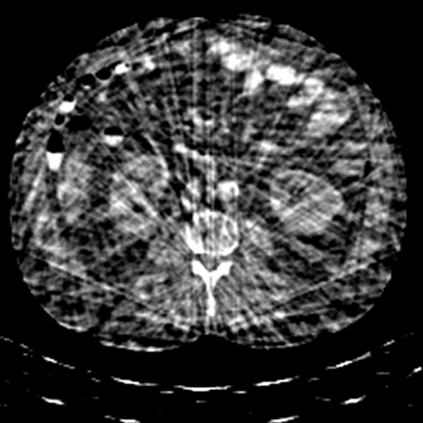

Sparse-view computed tomography (CT) -- using a small number of projections for tomographic reconstruction -- enables much lower radiation dose to patients and accelerated data acquisition. The reconstructed images, however, suffer from strong artifacts, greatly limiting their diagnostic value. Current trends for sparse-view CT turn to the raw data for better information recovery. The resultant dual-domain methods, nonetheless, suffer from secondary artifacts, especially in ultra-sparse view scenarios, and their generalization to other scanners/protocols is greatly limited. A crucial question arises: have the image post-processing methods reached the limit? Our answer is not yet. In this paper, we stick to image post-processing methods due to great flexibility and propose global representation (GloRe) distillation framework for sparse-view CT, termed GloReDi. First, we propose to learn GloRe with Fourier convolution, so each element in GloRe has an image-wide receptive field. Second, unlike methods that only use the full-view images for supervision, we propose to distill GloRe from intermediate-view reconstructed images that are readily available but not explored in previous literature. The success of GloRe distillation is attributed to two key components: representation directional distillation to align the GloRe directions, and band-pass-specific contrastive distillation to gain clinically important details. Extensive experiments demonstrate the superiority of the proposed GloReDi over the state-of-the-art methods, including dual-domain ones. The source code is available at https://github.com/longzilicart/GloReDi.